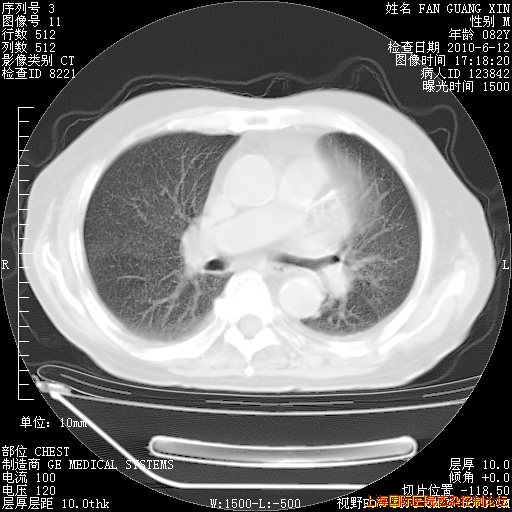

补发6月12日肺部CT肺窗

6月12日肺窗